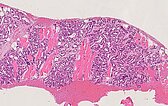

Um die Diagnose trotz der Hinweise auf ein infantiles Hämangiom klar zu sichern, bei differentem Verhalten der kutanen (fast rückgebildet) und der subkutanen Anteile (Wiedervergrößerung), wurde noch eine histopathologische Sicherung mittels Stanzbiopsie durchgeführt. Das Ultraschallbild zeigt die Biopsiepistolennadel innerhalb des Tumors am Oberarm.

Das histopathologische Übersichtsbild (40-fache Vergrößerung; HE-Färbung) des Stanzzylinders der Läsion zeigt Skelettmuskulatur, die diffus durchsetzt ist durch lobulär angeordnete, kapilläre Proliferate sowie einzelne Fettzellen (weiße, rundliche große Zellen), die ein Hinweis auf eine bereits stattfindende Involution sind.